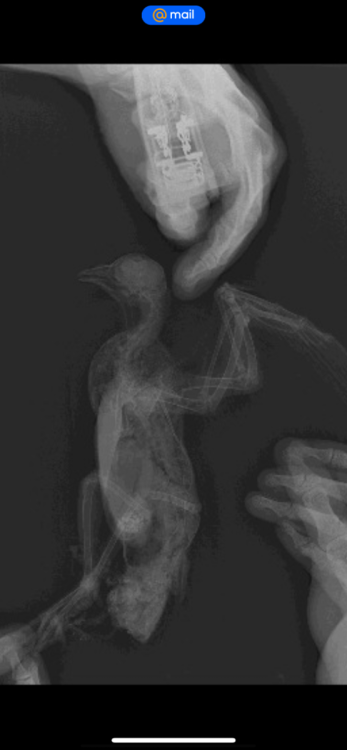

Здравствуйте. Неделю назад нашел голубя. Он просто лежал на спине и не мог встать. Подумал, что его на самокате сбили. Отвез к ветеринару, сделали рентген, который показал, что все норм. Вет.доктор который по птицам должен приехать в клинику через 5 дней. Пока взял его к себе. Он не мог стоять. Его косило и он падал опять на спину. Я его мыл, кормил и поил. Вот уже 4 дня как он стоит, ходит и нормально есть, и пьет. Но его все равно бывает наклоняет на правой бок. На крыле я заметил шишку. Наверное это область локтя. Почитал ваш форму и начал мазать ибупрофеном. Подскажите пожалуйста, что делать. Кто сталкивался с такой ситуацией. Вот симптомы: правое крыло нормально не складывается к спине, немного весит. Голубь бывает заваливается на спину через это же крыло. встать самостоятельно не может. Бывает трясется

рентген нужно чтобы посмотрела @Zosia